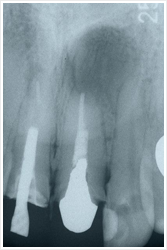

たとえばこんな感じです。

写真の方は炎症歯肉を切除したものです。

レントゲンの方は歯肉を開いて、根の深いところにある歯石や病巣を徹底的に除去したものです。

その結果、術前には根の周りに骨がなく(黒くみえる所)歯が浮いた状態だったものが、ほぼ1年後には失われた骨がずいぶんと再生し、歯もしっかりしてきました。